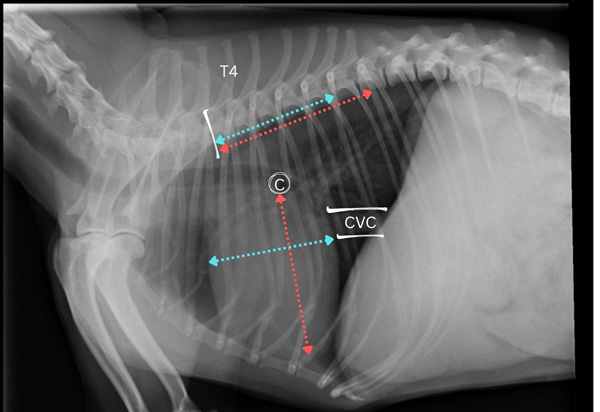

Figure 2: VHS. Lateral thoracic radiograph with carina (c), caudal vena cava (CVC), and spinous process of the fourth thoracic vertebra (T4) identified. Long axis of the cardiac silhouette (red line) is measured from carina to the apex of the heart and short axis (blue line) is measured from the cranial to the caudal border. These measurements are expressed in terms of vertebral body units using the cranial border of the fourth thoracic vertebra as the starting point.

To measure VHS:

- Obtain a good quality lateral thoracic radiograph centred over the heart.

- Identify the carina – a circular radiolucency dorsal to the base of the heart which corresponds to the bifurcation of the mainstem bronchi.

- Measure the long axis of the cardiac silhouette from the ventral border of the carina to the apex.

- Using the cranial border of the fourth thoracic vertebra as the starting point, express the length of the long axis of the cardiac silhouette in terms of vertebral body units (VBU) to the closest 0.1.

- Next, measure the short axis of the cardiac silhouette from the cranial border to the dorsal border at the widest part, perpendicular to the long axis.

- Express the length of the short axis in terms of VBUs, again using the cranial border of the fourth thoracic vertebra as the starting point.

- Add both numbers together to obtain the patient’s VHS10.